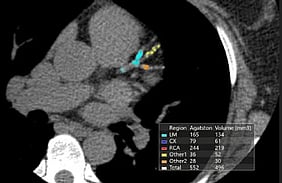

CT Coronary Angiography

CT coronary angiography offers a non-invasive way of imaging the coronary arteries. This test gives us an idea of calcium deposition within the coronary arteries and plaque formation due to fat deposition. Not only will it tell us if you have an important narrowing of a coronary artery but the knowledge of the extent of atheroma formation in the arteries will allow us to more accurately quantify your cardiovascular risk and will need for ongoing heart medications such as statins as well as plan for stent insertion if needed.

This is the preferred test for the assessment of chest pain. It cannot be used as a screening investigation for patients who do not have symptoms as it requires the administration of contrast. There is always a small risk of allergic reactions to contrast and this is not an acceptable risk of you have no symptoms. Calcium scoring is used in these cases.